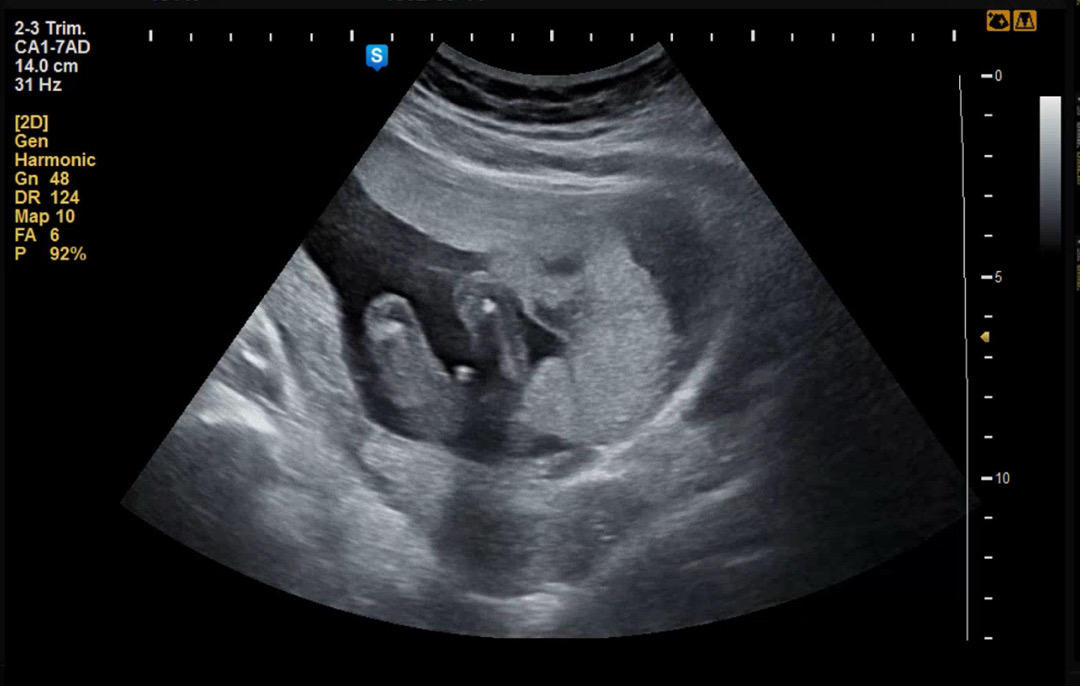

16주 초음파에요! 20주에 다시 보자 하시는데 아들이겠죠?!

16주 고추가 저렇게 작을 수도 있나요? 선배님들 알려주세요 !

아들맞아요..ㅋㅋㅋ